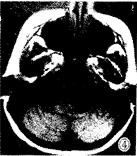

图1-3 女性,5岁,脑干明显增大膨突,横断面T1W低信号(图1),T2W高信号(图3),无明显强化(图2),肿块向前包绕基底动脉,向后推移第四脑室。图4-6 女性,6岁,横断面T1W低信号(图4),矢状面T1W增强(图5), 横断面T1W增强(图6),片状不均匀强化灶中见结节样强化。图7 男 性,6岁,横断面T1W增强,肿块环状强化呈葫芦形,中央低信号灶不强化。图8 女性,2岁,矢状面T2W,肿块向后压迫中脑导水管,第三脑室、侧脑室积水明显。

MRI:鉴于无颅骨伪影和多方位成像特点,MR是目前诊断胶质瘤和准确定位的最好方法,对于治疗计划的制定和随访有很大帮助,特征性MR表现为脑干胶质瘤呈膨胀性生长(图1~3),多为实质性,在T2加权图像上显示最为清楚,为明显高信号(图3),在T1加权图像上为低信号或低、等混合信号(图4),注射GD-DTPA后多数病灶 明显增强,少数无明显增强(图1~2),强化方式有:弥漫型(图未列出)、结节型(图4 ~6),沿着肿瘤边缘或囊变坏死区呈环状(图7)。肿瘤边界多较清楚,周围脑组织水肿多 较轻或不明显,肿瘤内部可发生小囊变或小出血灶,肿瘤向前生长包埋基底动脉(图1~3) ,部分脑干胶质瘤可位于中脑导水管附近,虽然较小,但可造成对中脑导水管的压迫,而继 发脑积水[3](图8),MRI较CT能更好地明确占位性病变的性质、部位、范围。